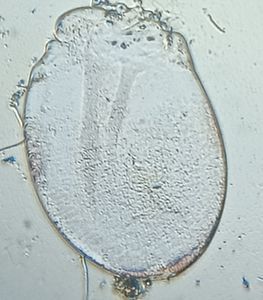

I am Dr.S.Meignanalakshmi, working as Professor, at the Directorate of Centre for Animal Health Studies, TANUVAS, Chennai-51. Working on Foldscope project on "Foldscope for diagnosis of Rumen Acidosis and parasitic infections in cattle" sanctioned by DBT